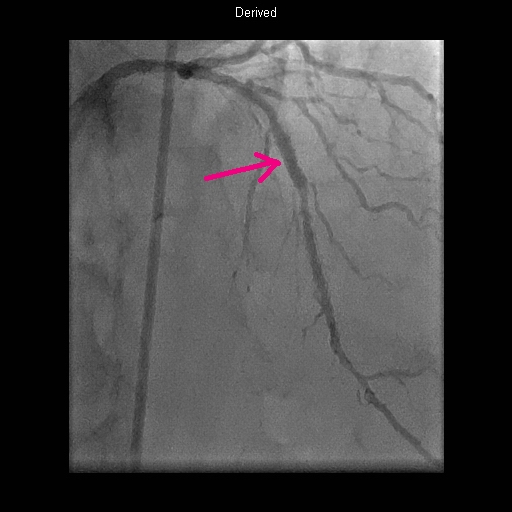

The angiogram was an extremely unpleasant procedure this time around. (Maybe not enough Valium?) The newer equipment blocked my view of the screen, for one thing, and a 'pressure test' using a sensor to read arterial pressure above and below the potential blockage and using drugs to simulate exercise, was very painful. But, all the the testing revealed that my original stent from 1996 was now about 75% blocked. and in fact that there was also a new blockage, lower in the left anterior descending, but it was not considered significant enough to treat surgically.

The upper arrow points to the blockage in old stent location, and the lower arrow shows the less significant blockage lower in the artery. A new medically coated stent (from Boston Scientific, a 'Promus Premiere'™,) was placed inside the old stent.